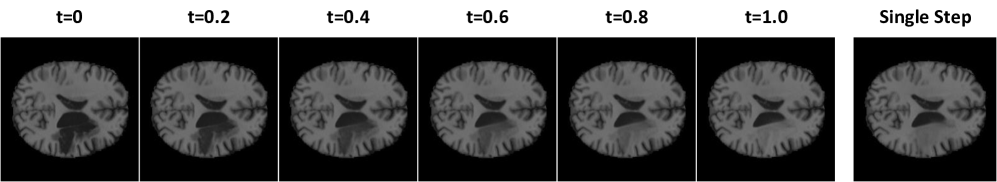

Refer to caption

Figure 3: Transition between an anomalous to healthy brain using 10 reverse ODE steps vs. a single step, showing that flows are well-rectified and effective in a single step.